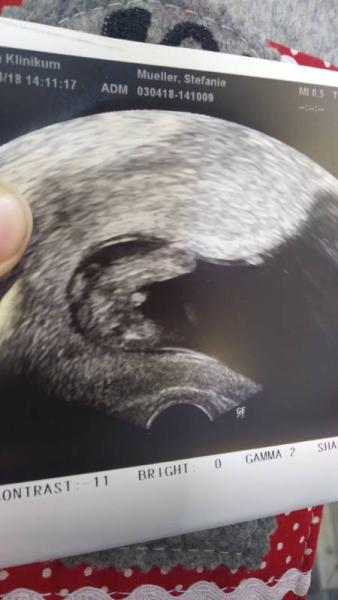

Von deinem Bild her würde ich aber jetzt auch Junge sagen. 15.Woche ist ja schon ein bisschen weiter. Bei meinen Söhnen hab ich in der 17.Woche ein eindeutiges Outing gehabt. Bild von meinem Sohn 17.SSW

Bild zu